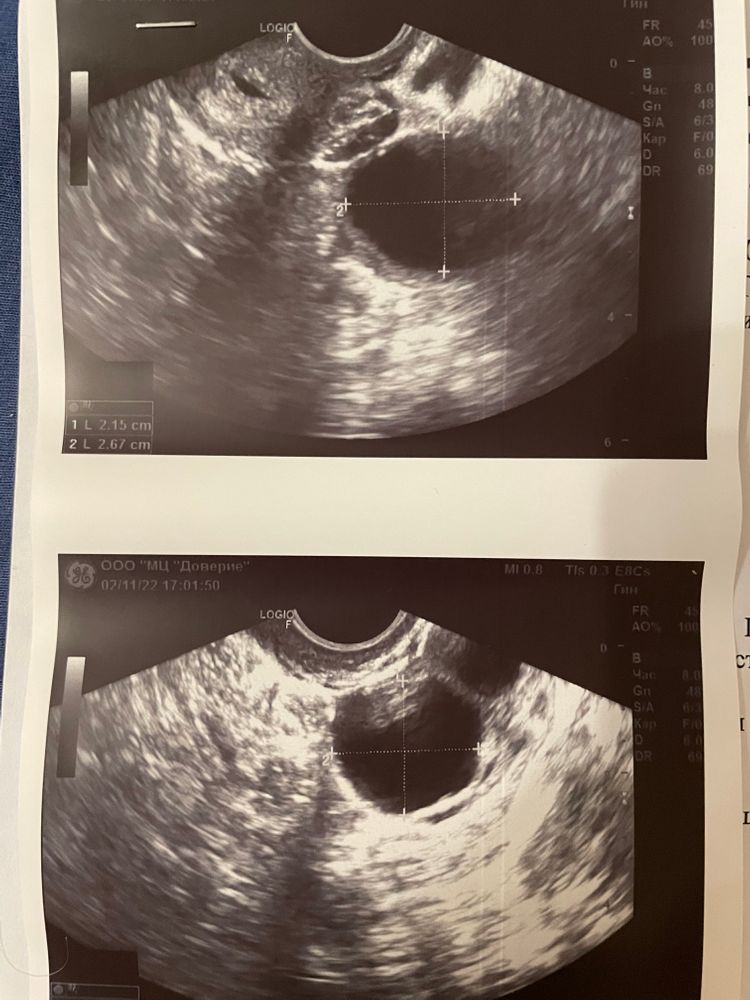

УЗИ 12 день цикла 02.11.2022

Оригинальный ли это препарат гонал ф? Не поздно колоть хгч при таких размерах ?????